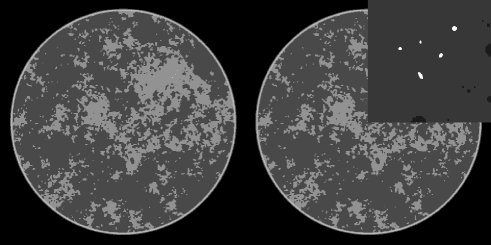

The complete phantom along with a blow-up of a region of interest (ROI) containing the micro-calcifications is shown in Fig. 1. The complexity of background is apparent, and although the phantom is indeed piece-wise constant, the gradient magnitude has 55,000 non-zero values due to the structure complexity. This number is relevant for the CS argument on the accuracy of TV-minimization. While there has been no analysis of CS recovery for CT-based system matrices, one can expect that at least twice as many samples as non-zero elements in the gradient magnitude will be needed for accurate image reconstruction with TV-minimization under noiseless conditions.

The breast phantom has four components: skin, fat, fibro-glandular tissue and micro-calcifications.

The latter two components are the most relevant and are now described in detail.

We refer all gray values to that of fat, which is taken to be 1.0.

The skin gray level is set to 1.15.

Fibro-glandular tissue: The gray value is set to 1.1.

The pattern of this tissue is generated by a power law noise model described

in Ref. [16]. The complexity of this tissue’s attenuation map

is similar to what one could find in a breast CT slice.

For the present study, the background fibro-glandular tissue, fat and skin are

represented with as a 1024x1024 digital phantom, from which projections are computed.

The reason for doing so, is that we want to isolate the issue of structural complexity

of the background, while removing potential ambiguity of

projection model mismatch.

Micro-calcifications: 5 small ellipses with attenuation values ranging from 1.8 to 2.1.

In this

case, the ellipse projections are generated from a continuous ellipse model, and

unlike the rest of the phantom, these projections are not consistent

with the digital projection system matrix. For these structures, object pixelization

is a highly unrealistic model because of their small size; hence we employ the

continuous model to generate their projection data.